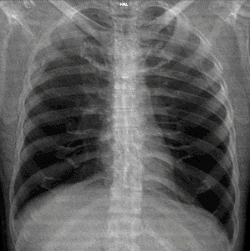

A normal posteroanterior (PA) chest radiograph of someone without any signs of injury. Dx and Sin stand for "right" and "left" respectively.

A chest radiograph, chest X-ray (CXR), or chest film is a projection radiograph of the chest used to diagnose conditions affecting the chest, its contents, and nearby structures. Chest radiographs are the most common film taken in medicine.